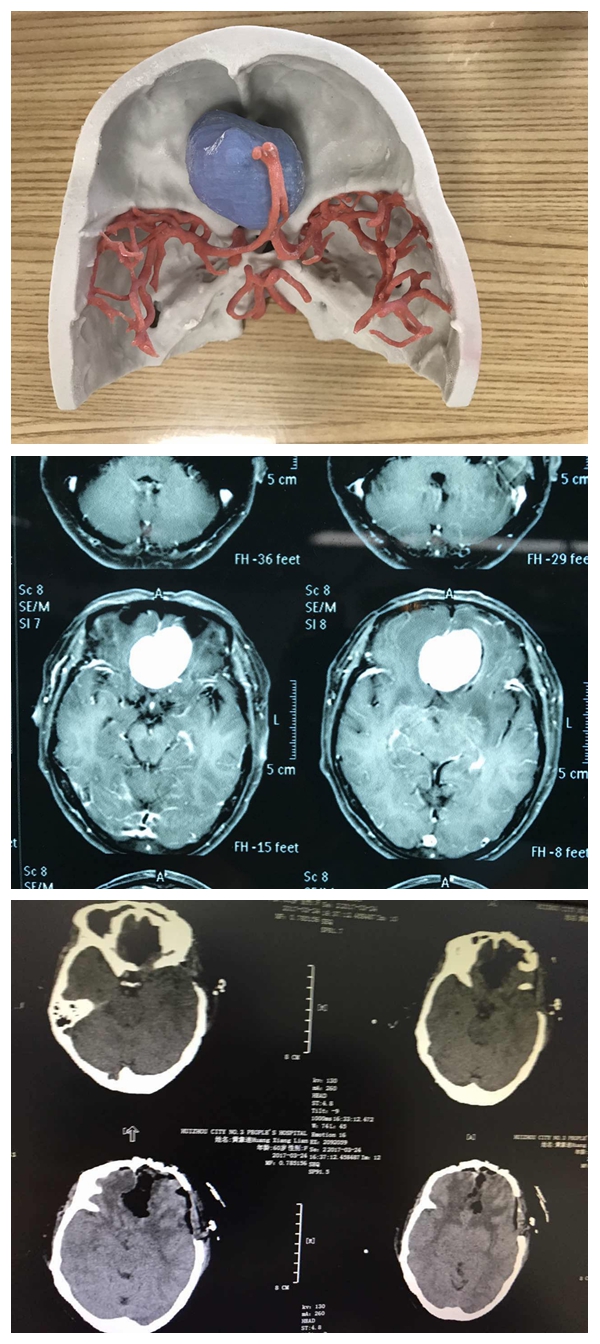

第三例脑肿瘤位于岩斜区,跨中后颅底,靠近中线,紧邻脑干全程,上起自天幕,跨天幕裂孔与中脑相邻;中间经过岩斜区,过内听道及中线区,与脑桥腹侧紧邻;向下达颈静脉孔及枕大孔外侧,与心跳及呼吸中枢延髓相邻。涉及到脑干及重要颅神经,包括动眼、滑车、外展、三叉、面、前庭蜗、舌咽、迷走、副及舌下神经全部被肿瘤影响,血管有大脑后动脉、小脑上动脉、小脑前下及后下动脉相邻,手术极其复杂,难度极大。患者术前有明显的面部疼痛及感觉运动障碍,彻夜难眠、痛苦不堪。对于该病例,李雪松主任高度重视,做了充分的评估和准备,术中使用神经电生理全程监护,显微镜下配合使用CUSA,雕刻式切除,操作都在毫米空间内完成,微创且无损伤,实乃精品佳作,患者术后症状完全缓解。

第三例3D模型、术前术后CT

据李雪松主任介绍,这一例可以说是世界级的高难复杂颅底肿瘤显微外科手术,肿瘤全切且脑功能及神经血管完美保留,神经功能保留完好,临床症状完全缓解,实属不易。